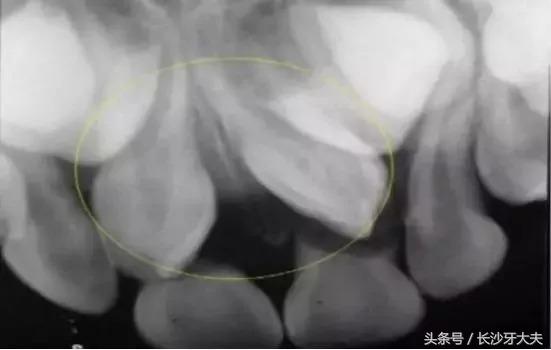

我不喜欢被约束,当普通牙齿都像小士兵一般整齐排队时,我却跑去探索骨内空间了。

偶尔插个小队,挡住去路不让门牙长出来,哈哈,想要从我这过,留下买路钱。

我力大无比,谁阻挡我,我就推开谁。